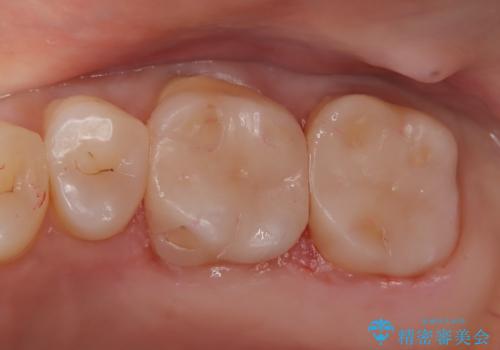

【メタルフリー】セラミックインレーの修復

金属を除去し虫歯の処置をしたあとセラミックインレーにて修復しました。

当院でのセラミックインレーは、ラバーダムを装着してセットしています。